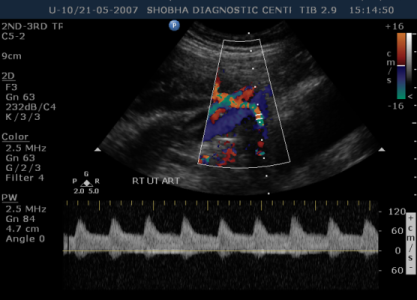

DOPPLER SONOGRAPHY / BIOPHYSICAL PROFILE

- Doppler Sonography gives information about blood circulation of the fetus.